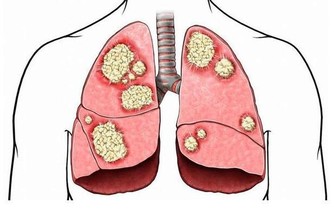

因為有了這一次治療頸椎和胸椎的經驗以後,發現很多患有頸椎病、腰椎病的人,在頸椎以下、腰椎以上相連接的椎體上,均存在著錯位,因此,得出一條重要結論:頸椎有病連著肺,腰椎有病連著胃。

這句話講的是什麼意思呢?頸七椎向下相連的是胸椎的一椎、二椎,這兩個椎體與肺相通,是通往肺的通路,當頸椎扭傷一定牽連到胸椎的一、二椎;腰椎向上相連的是胸十椎、十一椎、十二椎,十一椎、十二椎與脾、胃相通,是通往脾胃的通路,當腰椎扭傷一定牽連到胸十、十一椎。

胸椎的每個椎體,均與臟腑相通,是通往臟腑並為臟腑提供氣血的通路,當胸椎第一、二椎體發生了錯位,必然造成通往頸椎,肩膀的經脈運行受阻,氣血循環不暢,影響對頸椎和胳膊等部位的供血,導致通往頭部和肩部經絡受阻,血液循環不暢通,因而在頭部出現疼痛和胳膊發麻的病症。當錯位的胸椎經復位治療,一旦復位“開閘放水”,經脈通暢,活血化瘀,就迅速的滿足了頭部和胳膊缺血的需要,使頭痛和手指發麻的病症及時得到恢復。

頸椎下端和腰椎上端的這些部位,往往是在臨床中被遺忘的角落,所以,既影響頸、腰椎的治療,也影響與之相連病症的治療效果。醫者在治療頸椎腰椎的同時,一定要檢查鄰近胸椎椎體的排列狀態,頸椎的治療要注意到肺(胸一、二椎),腰椎的治療要注意到胃(胸十、十一椎),這是治療頸椎腰椎病症的關鍵。